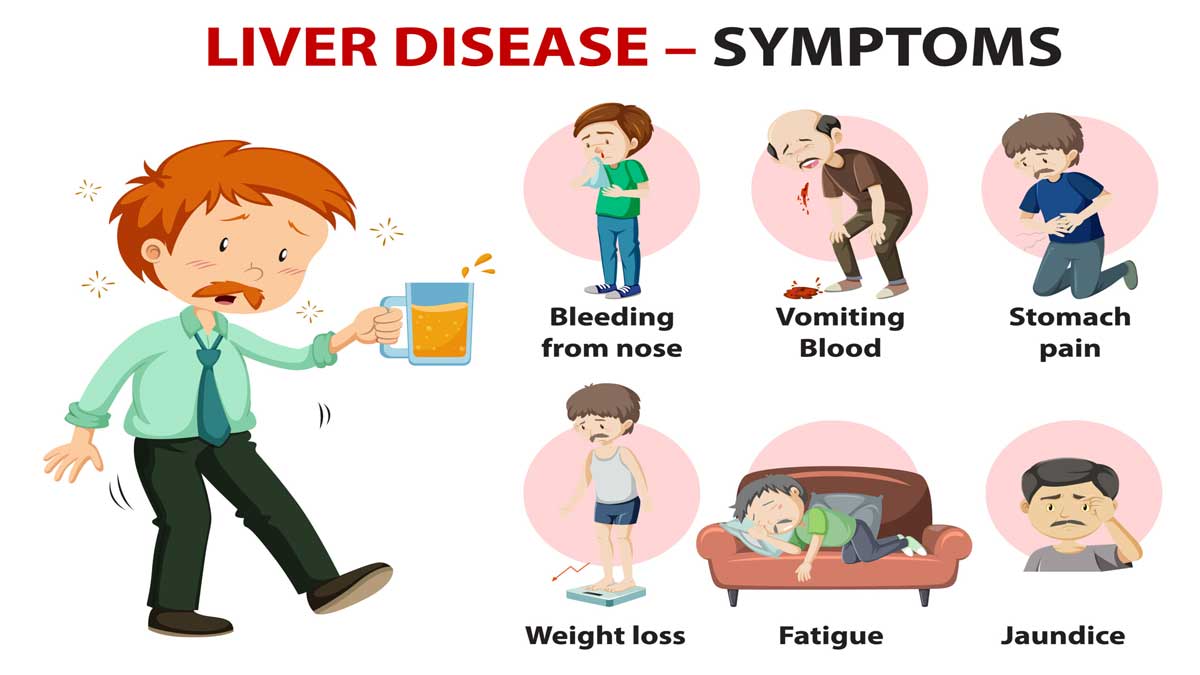

लिवर रोग के लक्षण

- अत्यधिक थकान

- भूख में कमी

- वजन कम होना

- पेट के ऊपरी हिस्से में दर्द और सूजन

- त्वचा और आंखों का पीला पड़ना (पीलिया)

- पेशाब का रंग गहरा होना

- उल्टी और मतली

- खुजली

- मानसिक भ्रम और भूलने की समस्या (सिरोसिस के मामलों में)